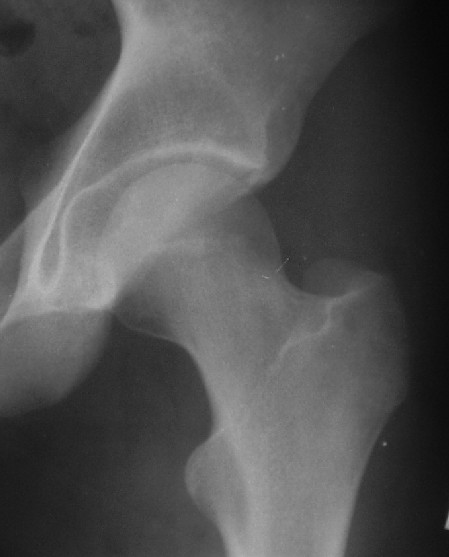

Для определения тактики - обязательно - нужен снимок в боковой проекции, скорее операция, в послеоперационном периоде разгрузка, прогноз при правильном ведении - хороший.

Почему отличаются снимки в прямой проекции после вправления здесь и на дополнительном приложении ?

Прямая проекция от 19.05 по всей видимости выполнена с фиксацией деротационной повязкой, что отразилось на положении бедра, кроме этого существенно изменилась позиция таза в сагиттальной и горизонтальной плоскости (постельный режим, уменьшение болевого синдрома).

О диагнозе: в отсутствие КТ, КТ с 3D реконструкцией, с наибольшей вероятностью можно предположить, что откололся фрагмент заднего сектора вертлужной впадины. С позиции современных представлений о механике тазобедренного сустава указанный сектор не является опорным в вертикальном положении. Казалось бы, его необязательно репонировать и фиксировать, тем более размеры фрагмента малы: